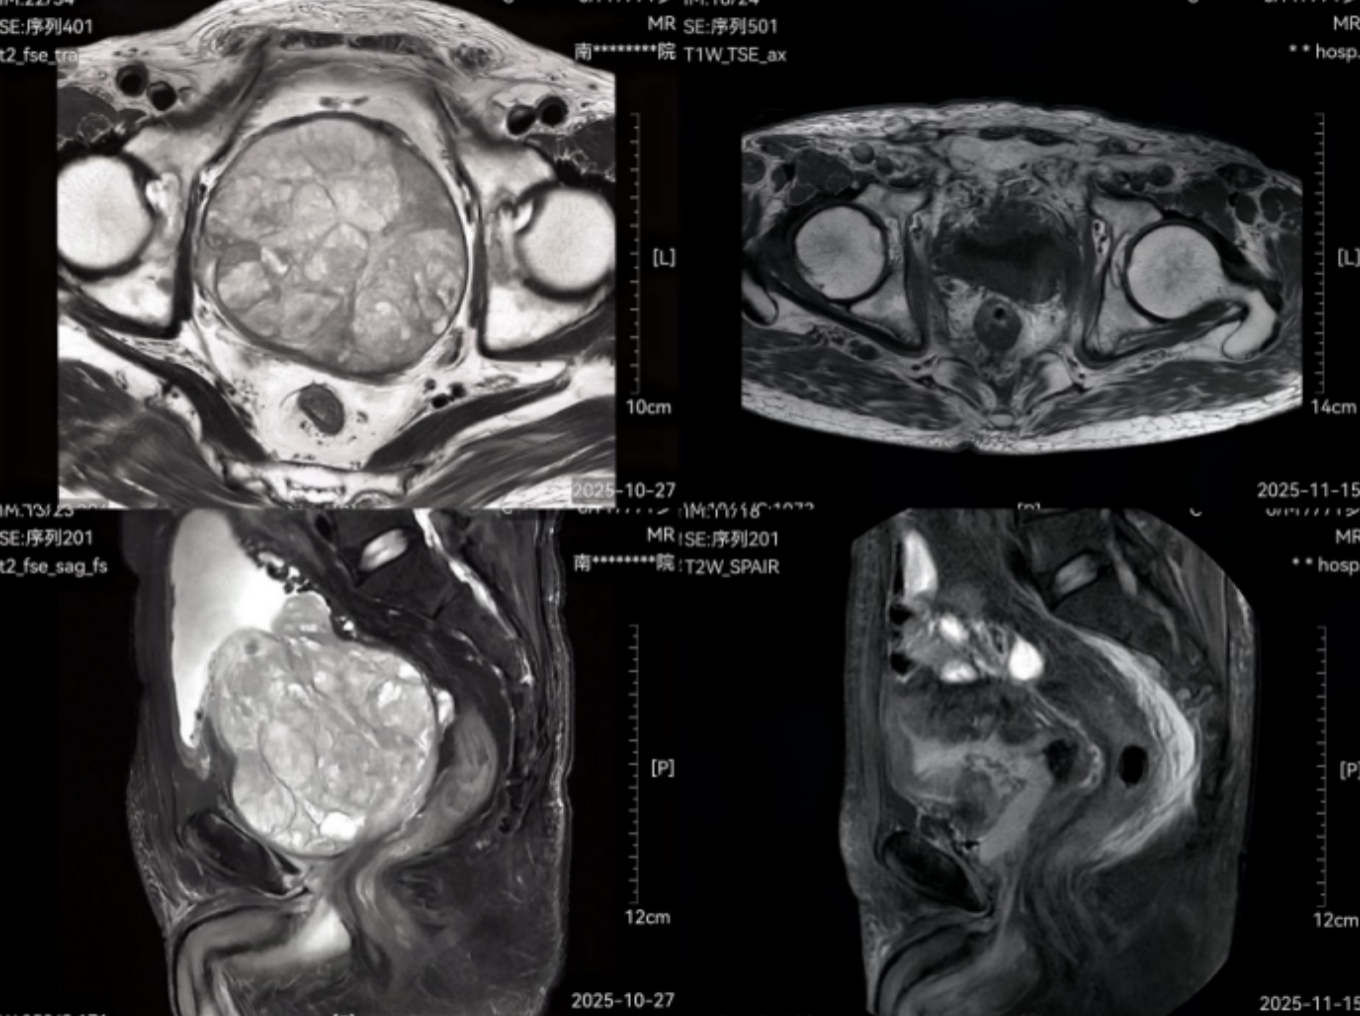

曹叔的这颗前列腺绝非普通的增生,重量达600克,尺寸约100mm×114mm×93mm,是正常前列腺(15-20克)的30倍。巨大的腺体不仅导致他严重尿潴留、反复血尿,还让排尿成为每日煎熬。更棘手的是,曹叔还患有持续性房颤、慢性阻塞性肺疾病等基础病,手术与麻醉风险陡增。他此前辗转多家医院,均因“高危体质+高危病灶”的双重挑战,医生常常不敢给他做手术。“风险太大。”

这项技术就像在微创通道里“剥橘子”,沿着前列腺外科包膜的天然平面,将增生腺体完整、精准地剥离并取出。相比传统电切术,它具有切除彻底、出血少、恢复快、远期复发率极低的优势。手术团队经过3小时的精细操作,把这颗困扰患者多年的“超级前列腺”成功拆除。术后曹叔恢复迅速,排尿通畅自如,目前已康复出院。